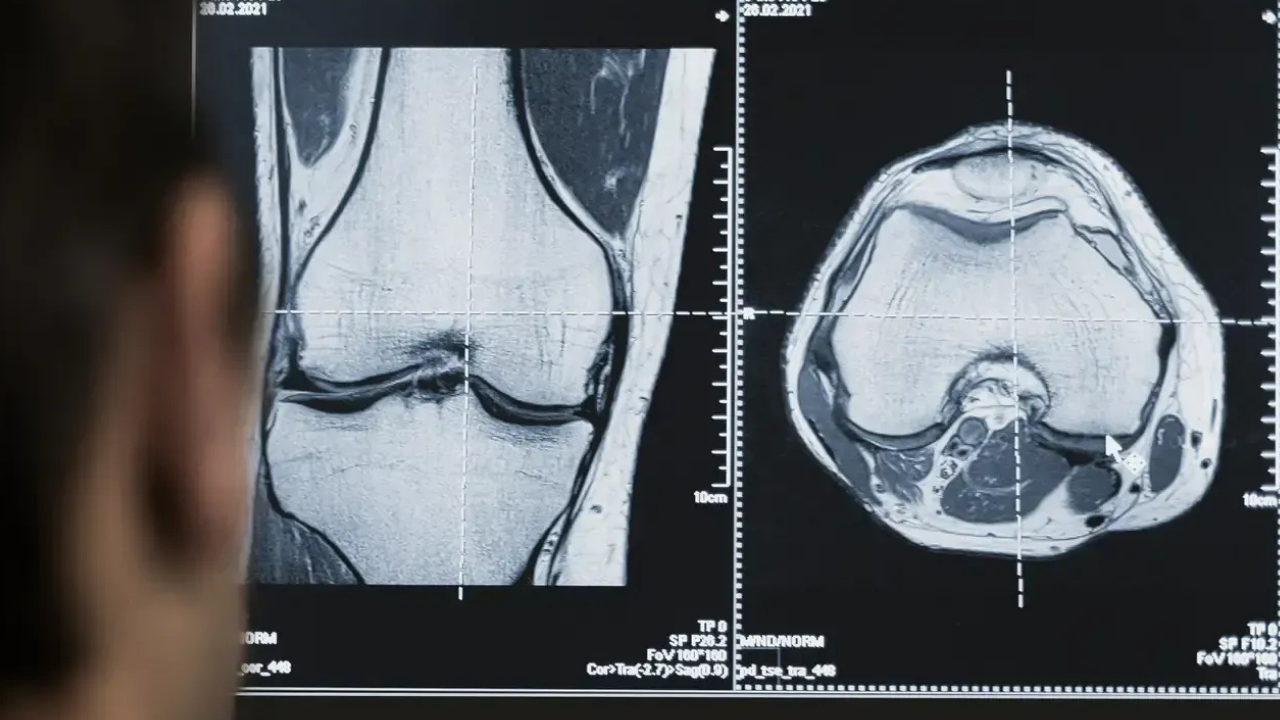

Skandalın merkezinde, hastanenin radyoloji hizmetlerini özel şirketlerden hizmet alımı yoluyla sağlaması ve bu süreçte yanlış tanı raporlarının verildiği iddiaları yer alıyor. Bazı hastaların MR ve tomografi sonuçlarının eksik veya hatalı raporlandığı ve bunun ciddi sağlık sorunlarına yol açtığı ileri sürülüyor. Bir hasta, daha önce beyin kitle büyümesini gösteren görüntüsünün son raporda “normal” olarak raporlandığını belirterek büyük mağduriyet yaşadığını dile getirdi.